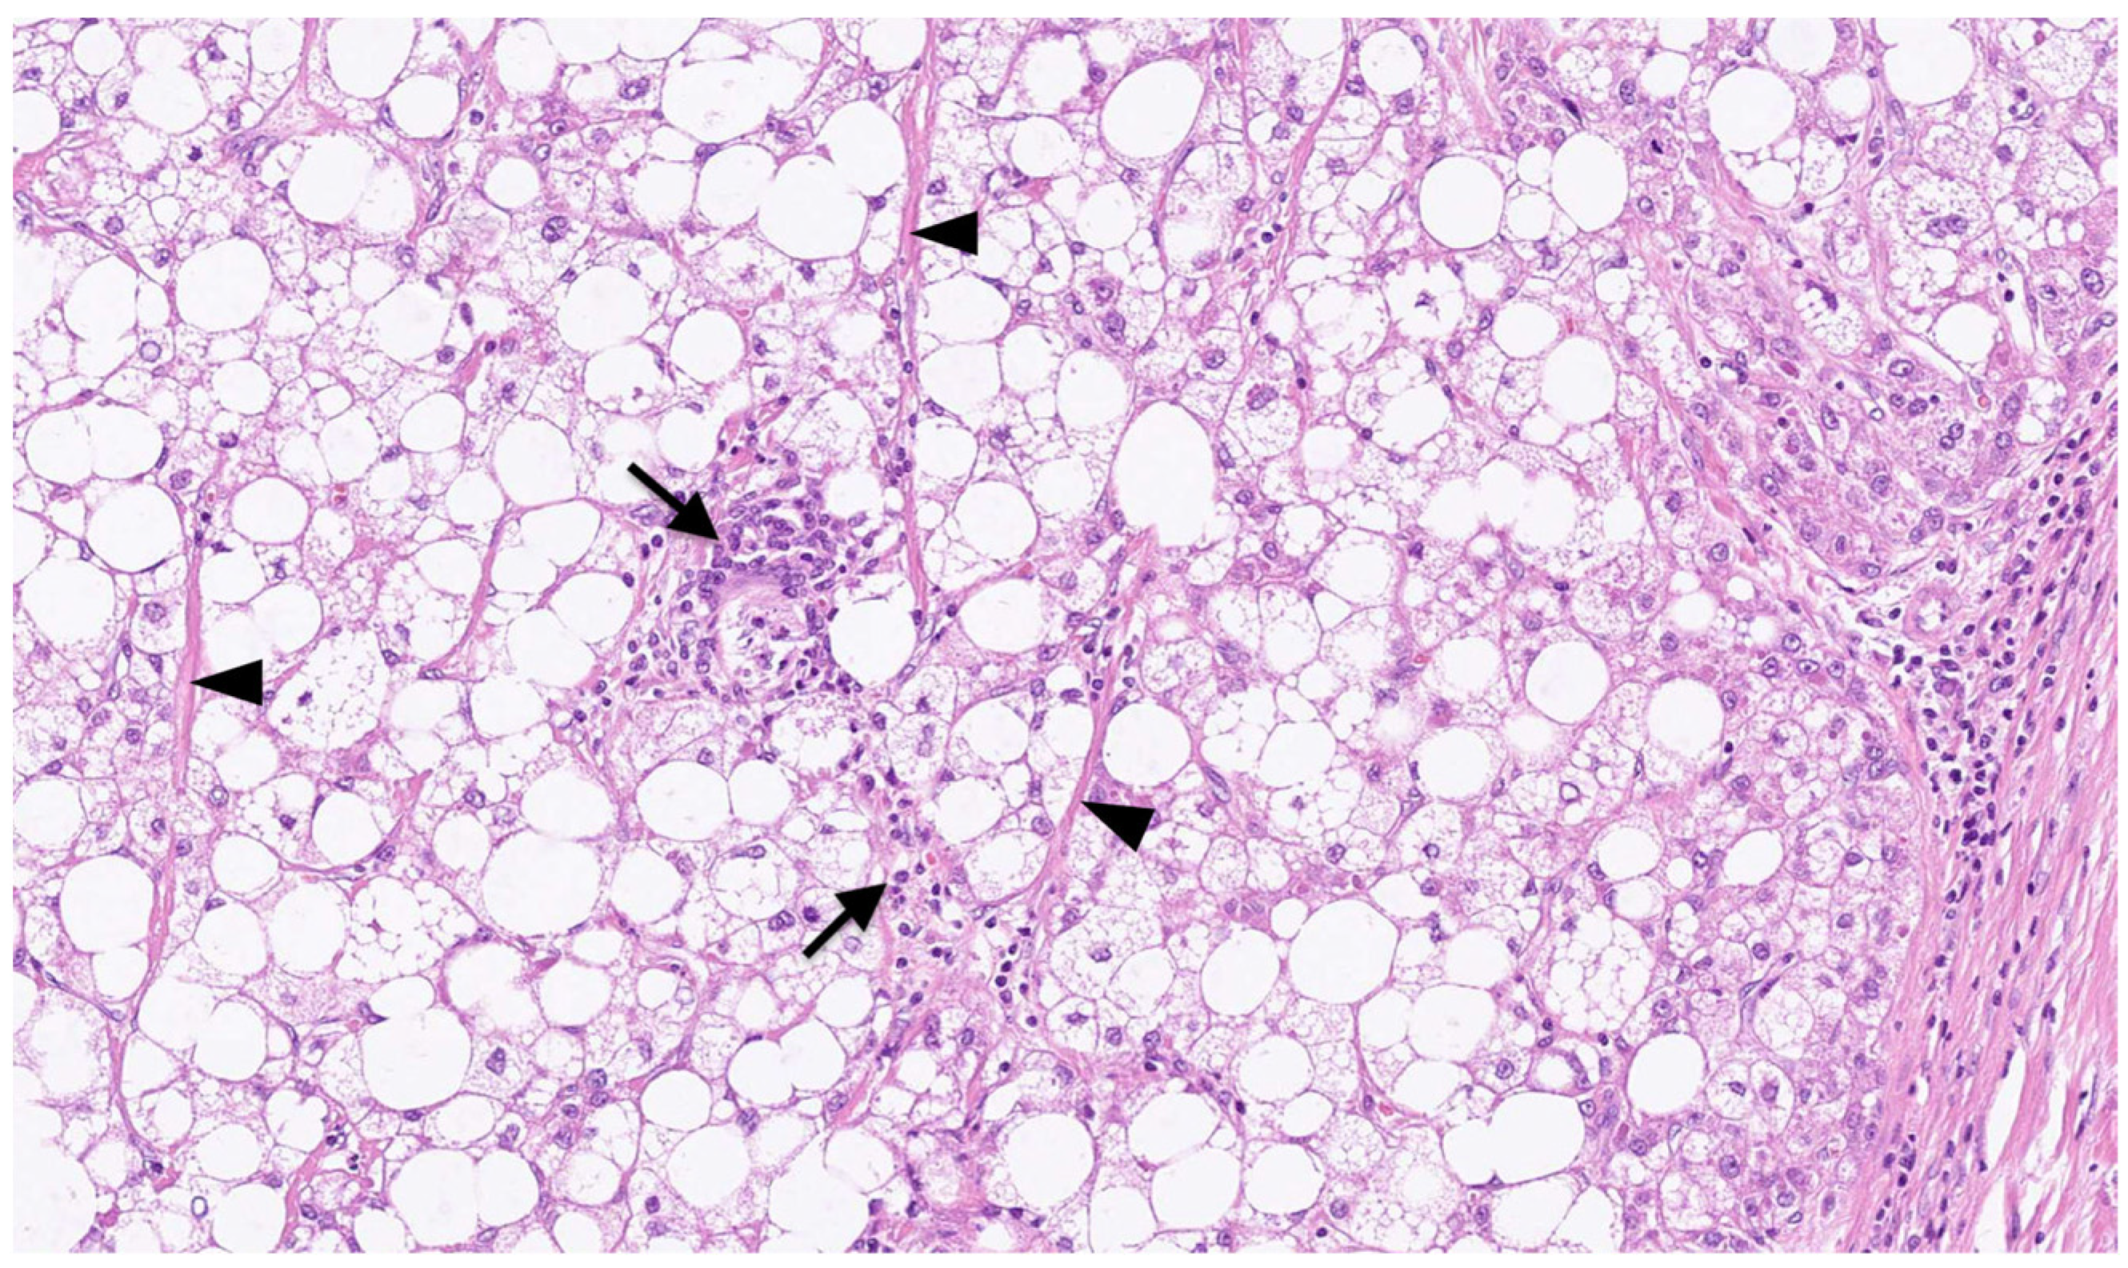

Figure 2.

Microscopic appearance of SH-HCC. Large droplet steatosis, inflammation (arrows), and fibrosis (arrowheads) are observed in the tissue of hepatocellular carcinoma (HCC). This is an original photomicrograph with a magnification of ×125.

On macroscopic examination, SH-HCC is golden-yellow in color, reflecting steatosis, and is slightly firmer than conventional HCC, reflecting fibrosis [31] (Figure 1). The tumors are nodular and well demarcated, and the size ranges from 0.5 to 11 cm [15]. Microscopically, SH-HCC is characterized by large-droplet steatosis, inflammation, fibrosis, ballooning, and Mallory–Denk bodies, which are characteristic features of steatohepatitis (Figure 2 and Figure 3). The pattern of fibrosis is trabecular (thick bundles of fibrous tissue within the tumor) or pericellular (thin strands of fibrosis with a “chicken-wire” appearance) [30]. Although the diagnostic criteria for SH-HCC have not been established, at least 5% or 50% of the tumor area must show steatohepatitic features [15,30,31]. SH-HCC displays a less aggressive histological phenotype, lacking satellite nodules and microvascular invasion [34].